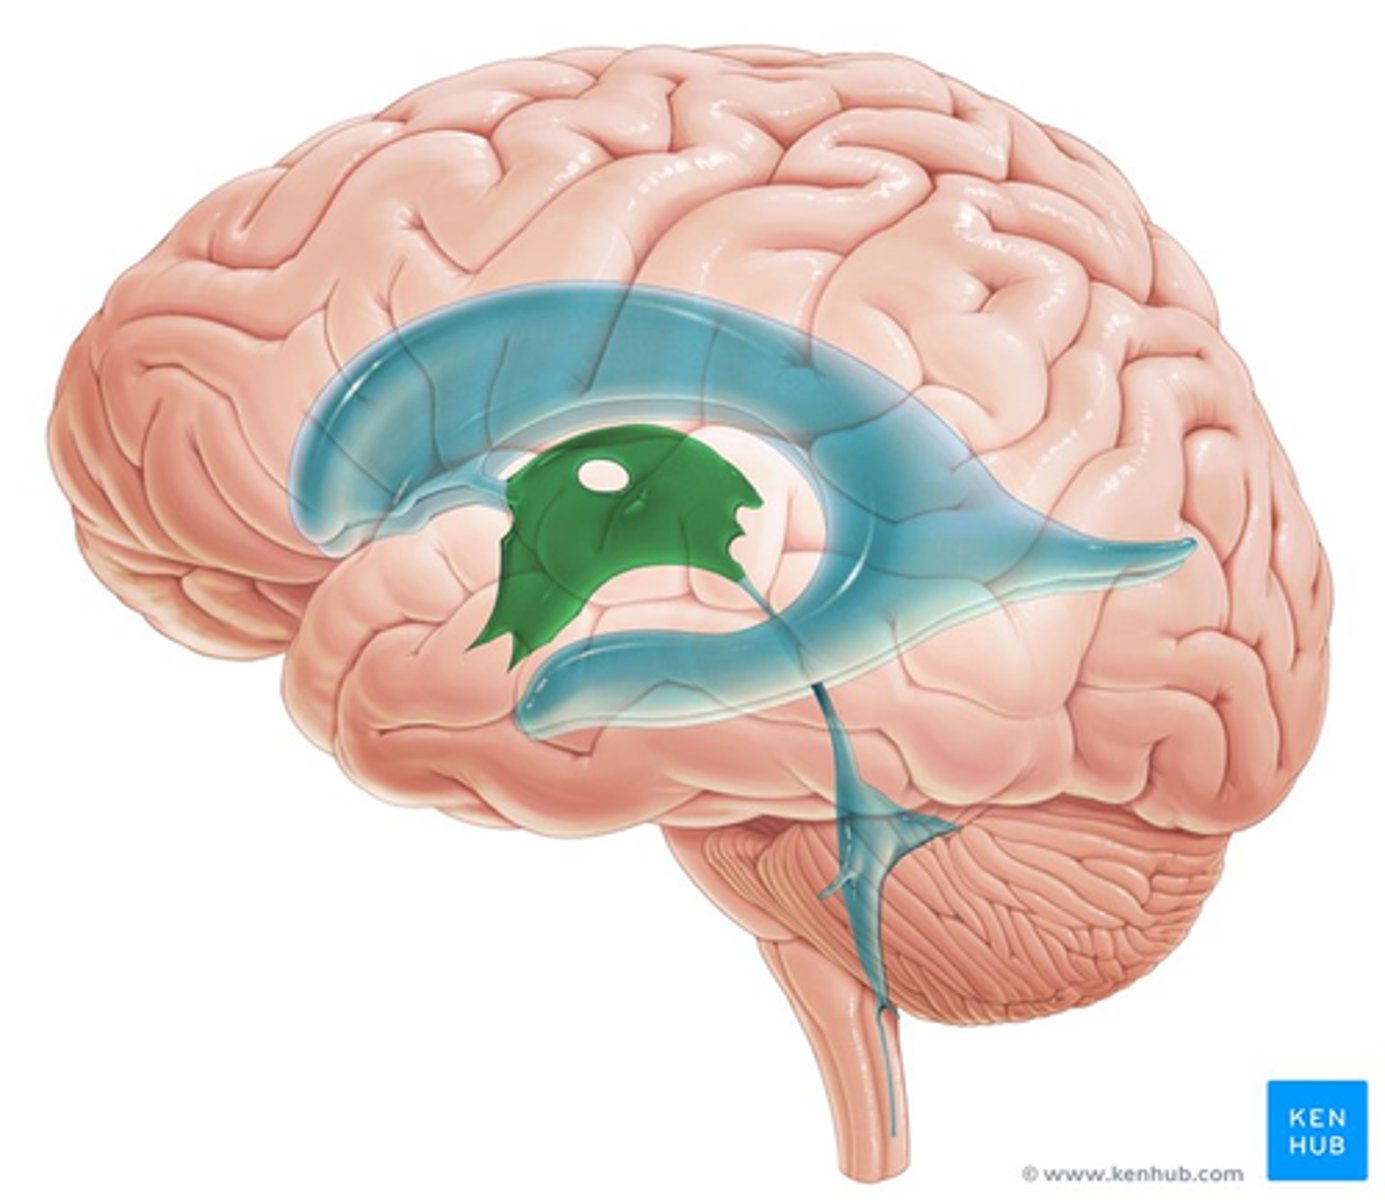

What connects the third and fourth ventricles?

cerebral aqueduct

What is the floor of the 4th ventricle?

tegmentum pons

What is the superior medullary velum?

membrane that forms the superior portion of the 4th ventricle roof

image -- 7

What is the inferior medullary velum?

membrane that forms the inferior portion of the 4th ventricle roof

image -- 1

Where does the 4th ventricle end?

medulla

cranial medulla -- "open" half

caudal medulla -- "closed" half